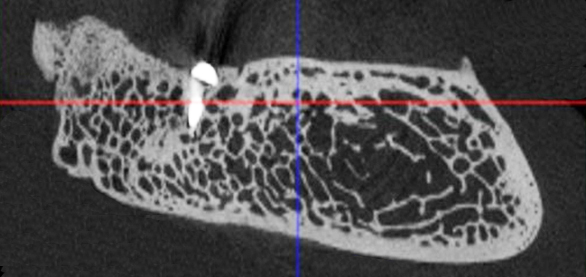

Для изучения структуры костей и определения их минеральной плотности использовали рентгеновский компьютерный микротомограф Skyscan 1176 (Bruker microCT, Бельгия). Сканированные объекты реконструировались в программе Nrecon (1.7.4.2, Bruker-microCT, Бельгия). 3D-визуализация полученных результатов в зависимости от рентгенологической плотности проводилась в программе CTvox (3.3.0r1403, Bruker-microCT, Бельгия) (рис. 8).

Рис. 8. Оценка результатов эксперимента с помощью компьютерной микротомографии. Визуализация в программе DataViewer и CTvox